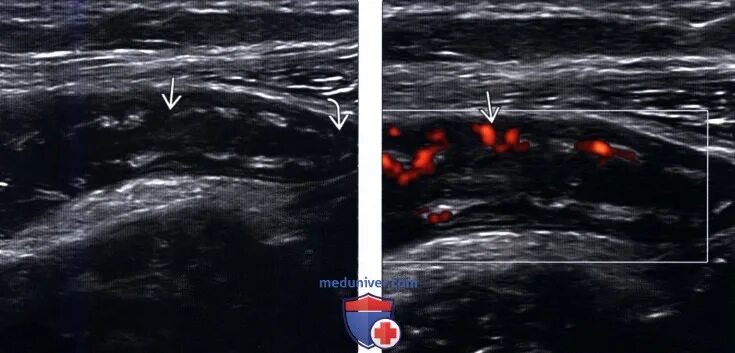

Какое узи при аппендиците